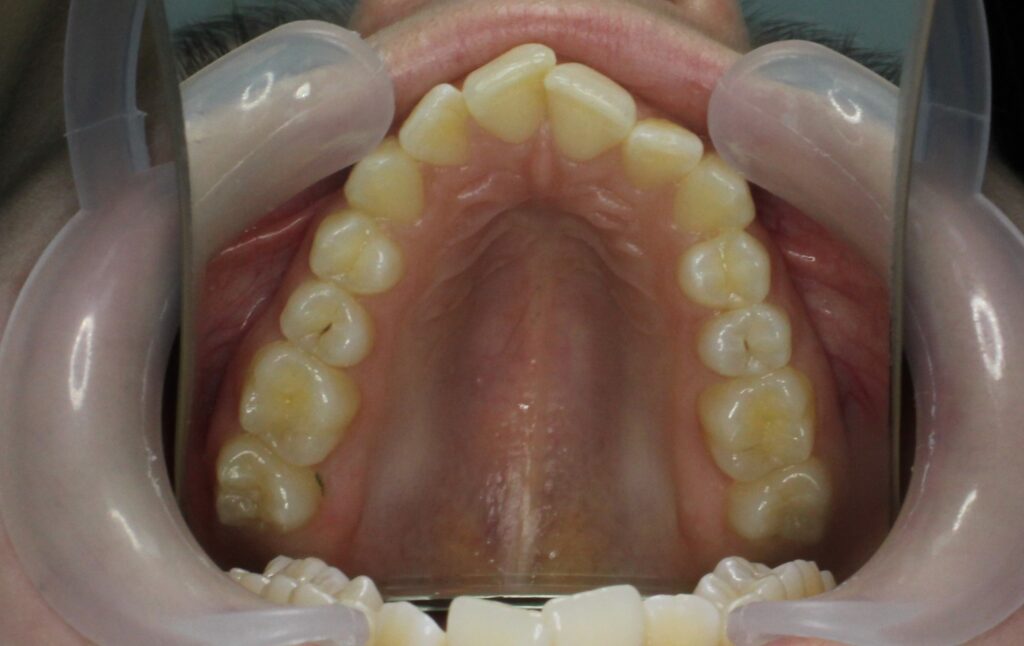

Ситуация до лечения

Жалобы: Пациентка обратилась с жалобами на неровное положение передних зубов.

Диагноз: дистальный прикус, сужение верхнего и нижнего зубных рядов, скученность фронтальной группы зубов на верхней и нижней челюсти.

пациент до лечения брекетами